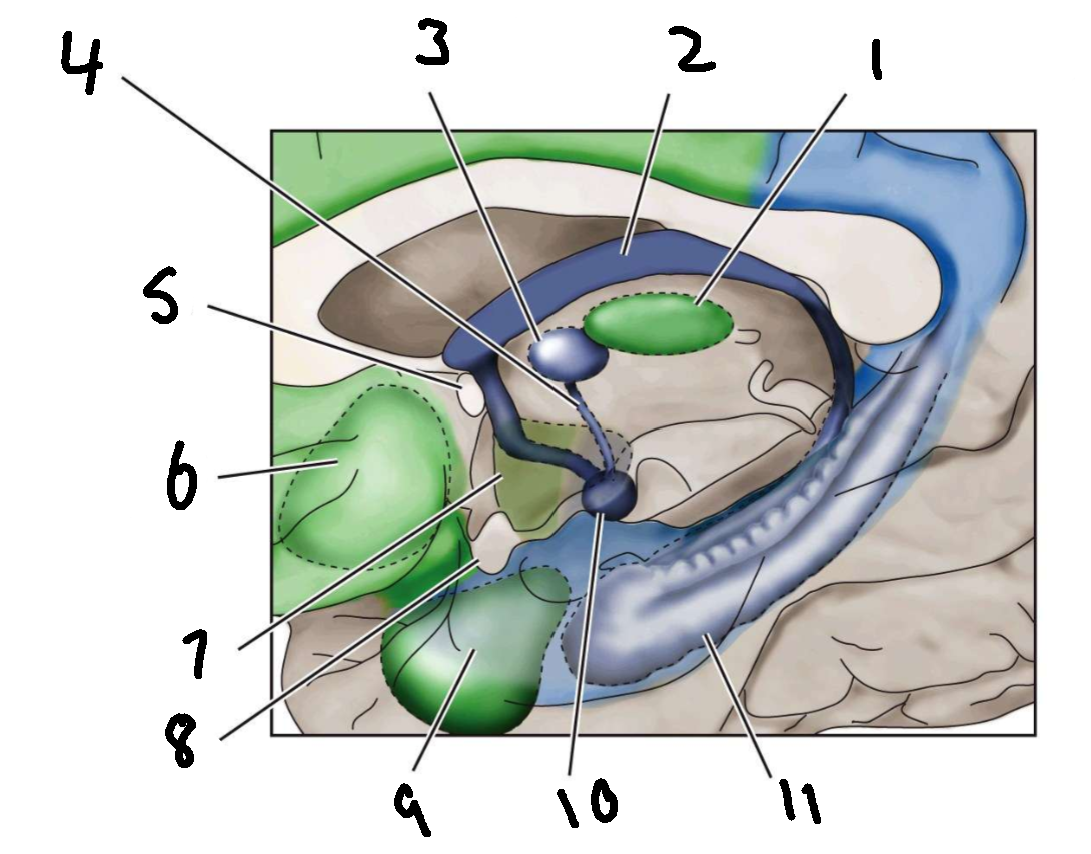

What is 1?

mediodorsal nucleus of the thalamus

What is 2?

fornix

What is 3?

anterior nucleus of the thalamus

What is 4?

mammillothalamic tract

What is 5?

anterior commissure

What is 6?

ventral basal ganglia

What is 7?

hypothalamus

What is 8?

optic chiasm

What is 9?

amygdala

What is 10?

mammillary body

What is 11?

hippocampus